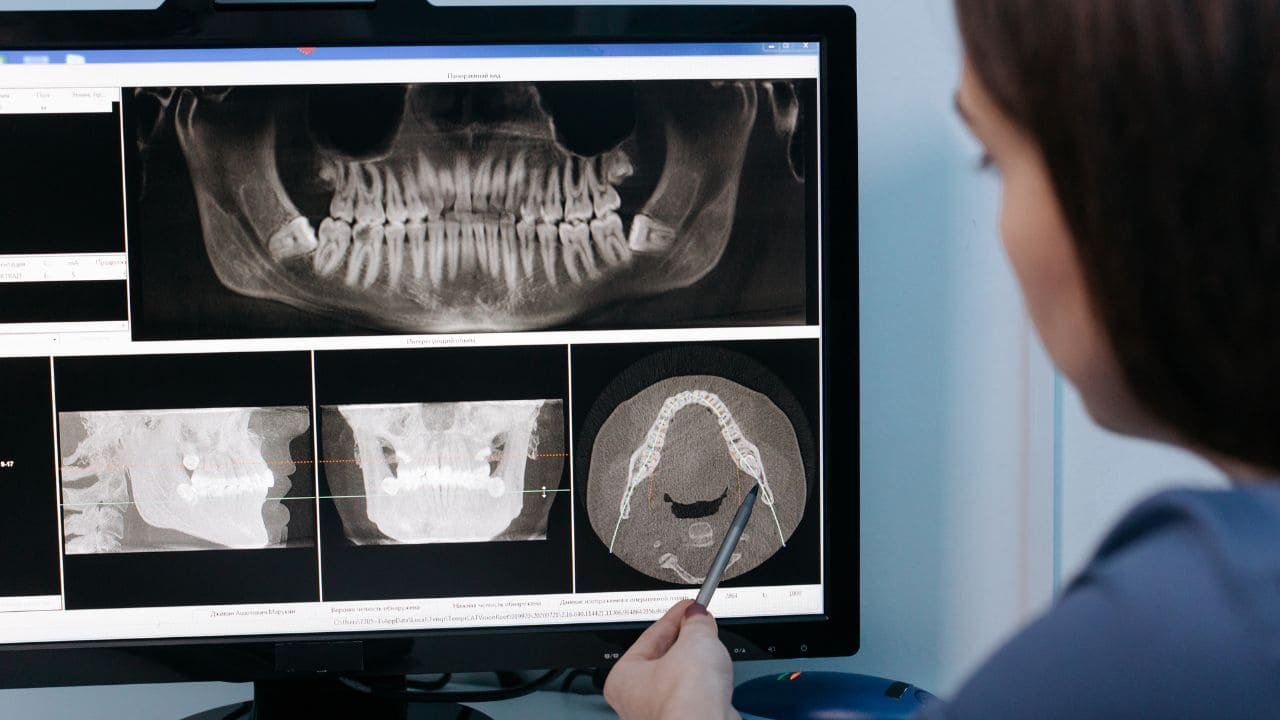

3. Les radiographies si nécessaires : Petits clichés numériques (très faible dose de rayons) pour détecter les caries entre les dents ou vérifier le développement des dents permanentes.